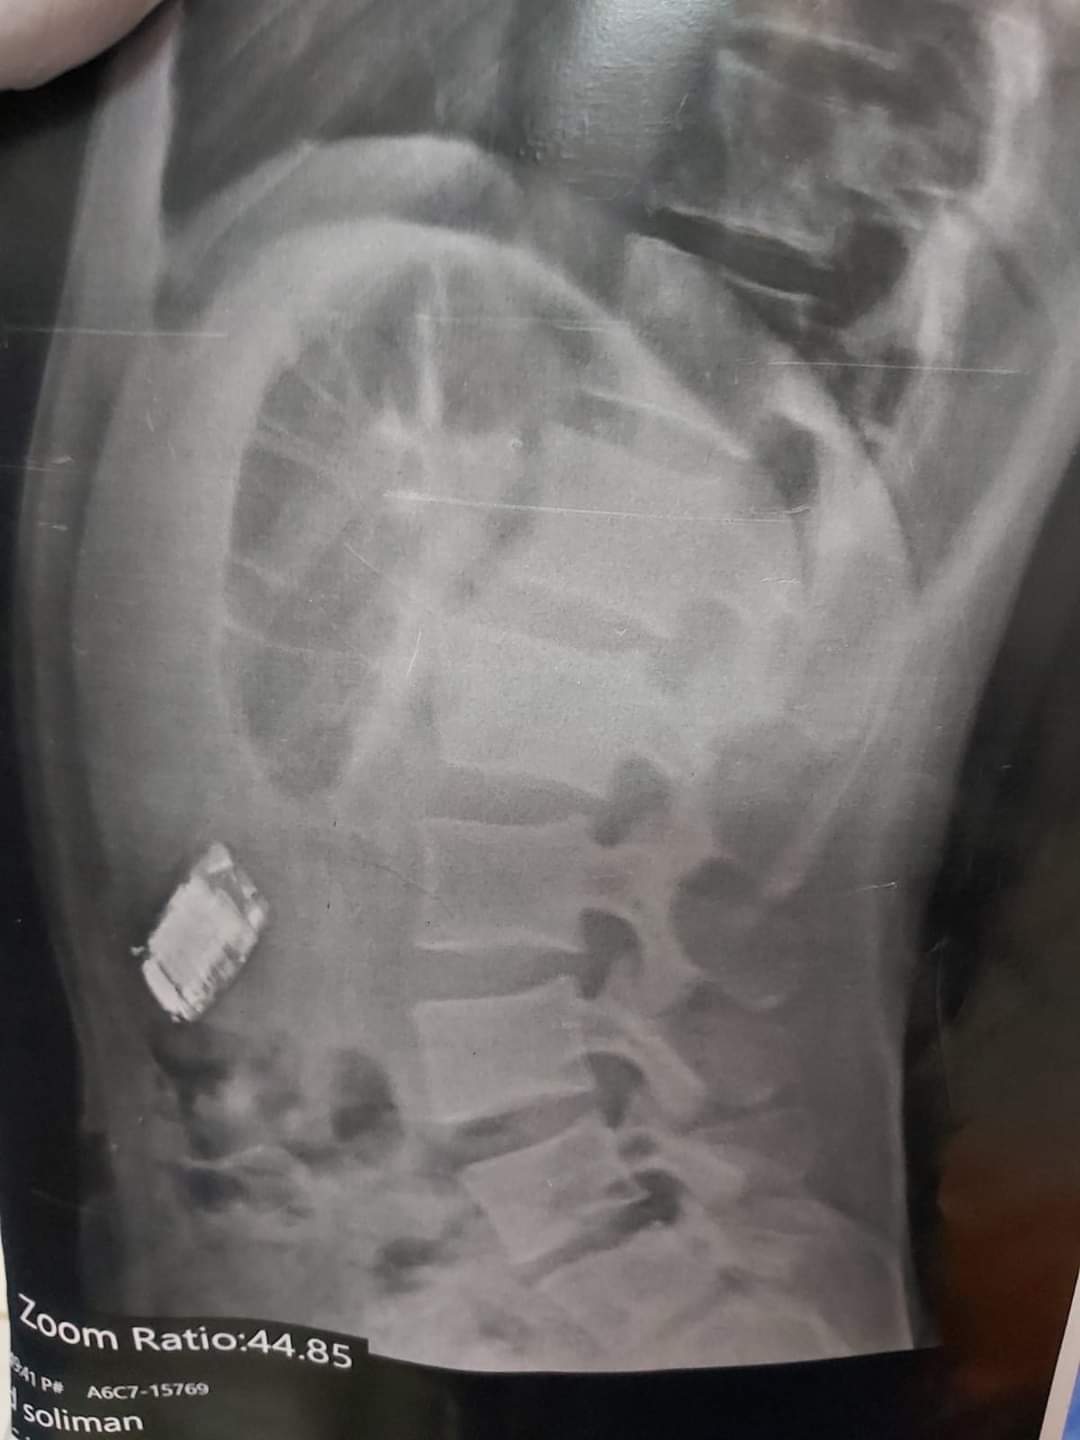

نجح أطباء مستشفى شبين الكوم التعليمي، بمحافظة المنوفية، في استخراج تليفون محمول صغير من بطن سجين بسجن شبين الكوم، بعد اتخاذ الإجراءات الطبية اللازمة واستدعاء عدد من التخصصات المختلفة.

وكشف بيان من مستشفى شبين الكوم التعليمي، وصول قوة من سجن شبين الكوم ومعها مسجون يبلغ من العمر 20 عاما ابتلع موبايل صغير، وبعد عمل الفحوصات والتحاليل اللازمة بالمستشفى، تم تحضيره لدخول العمليات على الفور توجه فريق من أطباء مناظير الجهاز الهضمي على أعلى مستوى من المهارة بقيادة الدكتور عماد الديب، وتم استدعاء أطباء التخدير والكبد والأنف والأذن بالمستشفى تحسبا لأى طارئ.

واستغرقت العملية فترة طويلة حتى تم استخراج الموبايل وهو ملفوف بكيس بلاستيك، وتمت العملية بنجاح في تحدى جديد لتقديم الخدمة الطبية الجيدة والفائقة للمرضى، بمشاركة كل من الدكتور عماد الدي، والدكتور أحمد صلاح، والدكتورة رباب بدران، والدكتور عبد الغنى عيش، والدكتور محمد عياد، والدكتورة مروة هيكل، ووجود طاقم من التمريض.